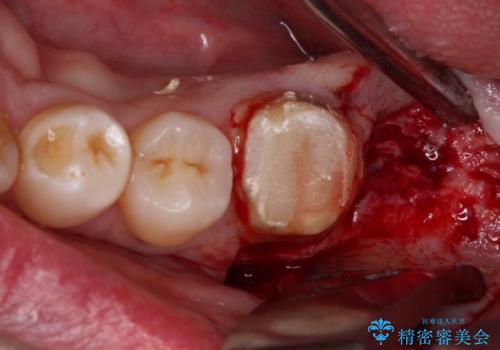

- 近医にて奥歯の抜歯が必要と言われたとのことで来院された患者様です。

診査の結果、歯が破折しており、抜歯が必要な状態でした。

インプラントにはストローマン社のSLActiveを使用し、埋入から補綴までおよそ3か月と、短期間で治療を進めることができました。